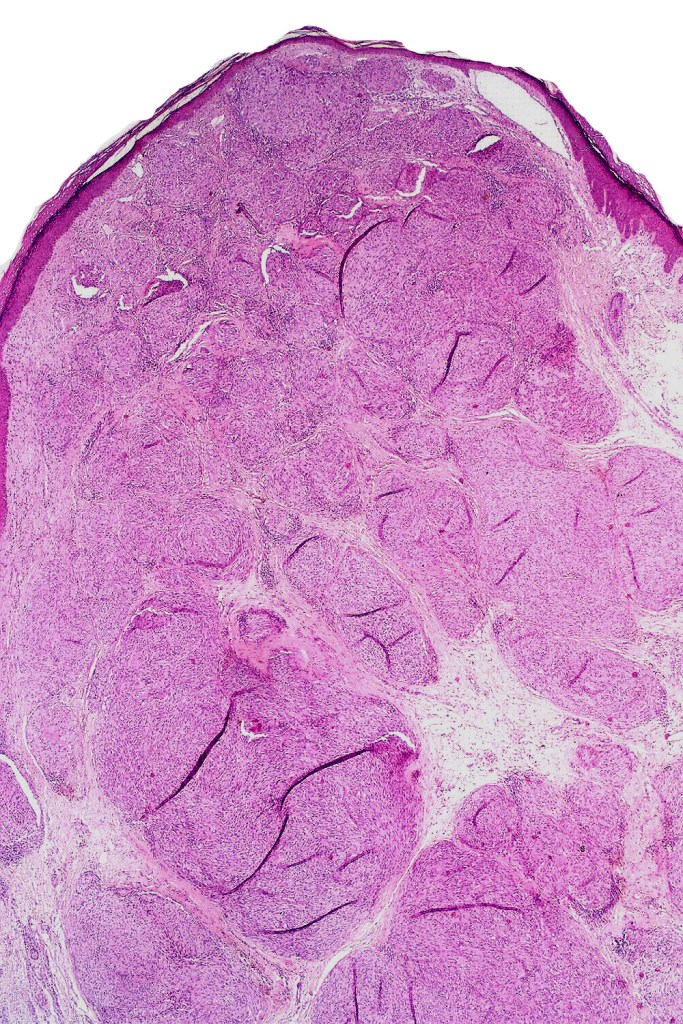

•Sharply circumscribed (begins and ends with a nest), symmetrical dome-shaped lesion. Symmetry is both horizontal and vertical (see image below)

•Wedge-shaped with the base uppermost or sometimes plaque-shaped silhouette